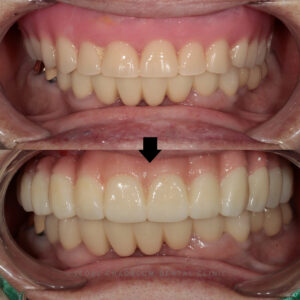

24.07.11 / 24.11.30 / 24.12.07

치료 전후 사진입니다.

환자분께서는 틀니만 쓰시다가

임플란트를 쓰니 어색해하셨으나,

적응기간을 거치고 틀니보다

편하다며 만족해 주셨습니다.

하지만 임플란트 하방으로

음식물이 저류 되고

관리가 잘 되지 않아 정기검진 오실 때마다

체크하며 치간칫솔 교육을

진행해 드렸습니다.